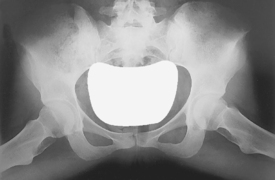

• Supine, pelvis centered to centerline, legs extended

• Both feet, knees, and legs equally rotated internally 15° (secure with tape if necessary). Support under knees for comfort.

• Ensure no rotation of pelvis (ASISs equal distance from TT).

• Center IR to CR. (Include entire pelvis.) Shield gonads (if it doesn’t compromise study).